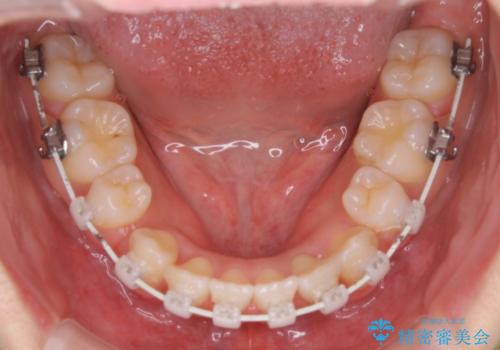

- 矯正装置

- 審美装置(ワイヤー)

- 出っ歯が気になるとご相談にいらした方です。抜歯して歯を並べました。深かった噛み合わせも改善させることが出来ました。